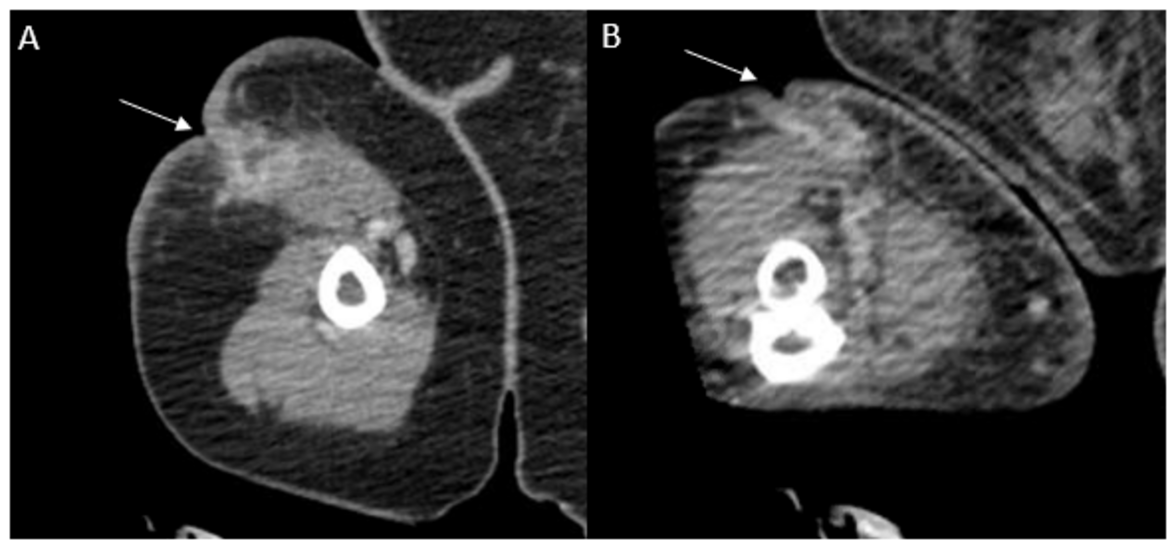

Для дальнейшей оценки степени распространения инфекции кожи и мягких тканей была проведена компьютерная томография плеча и предплечья, которая выявила толстостенное скопление жидкости, свидетельствующее о формировании абсцесса в месте операции, охватывающее как плечо, так и предплечье пациентки (илл. 2). Также была проведена консультация со службой пластической хирургии, которая обратила внимание на старую йодоформную марлю в области расхождения раны с окружающей эритемой (илл. 1В); однако нагноения из этих областей не было.

Иллюстрация 2. Компьютерная топография с контрастированием. На снимках плечевой кости (изображение A) и предплечья (изображение B) выявлено вероятное образование абсцесса (белые стрелки) длиной около 6,8 см и размером около 1,5 см в наибольшем измерении как на плечевой кости, так и на предплечье.